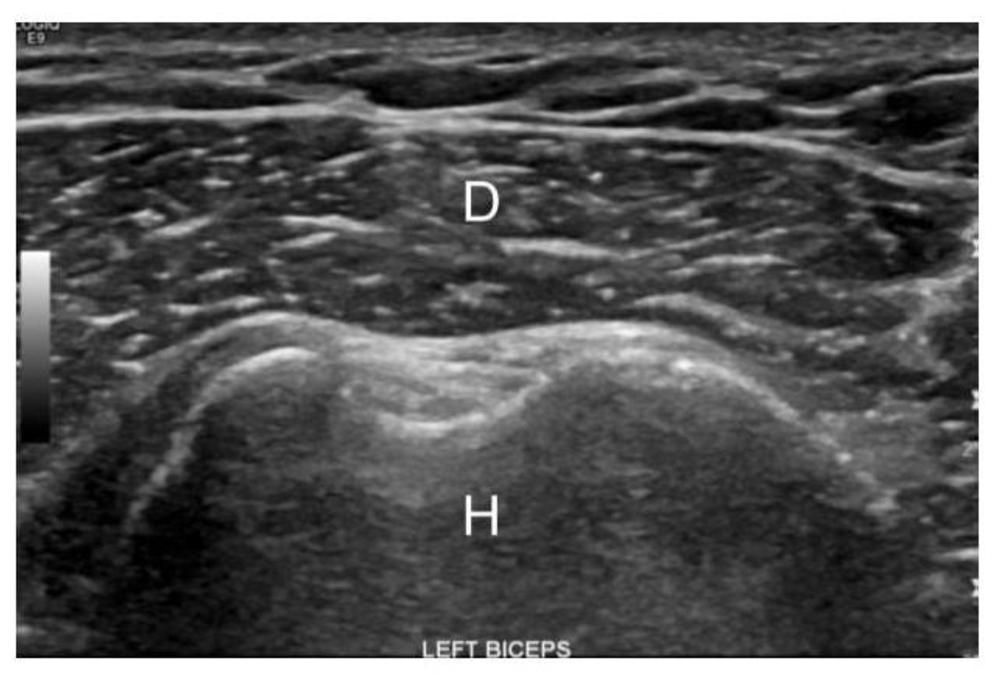

Figure 2. Image of the normal deltoid muscle in an obese, non-diabetic patient. D - Deltoid, H - Humerus

High-res (TIF) version